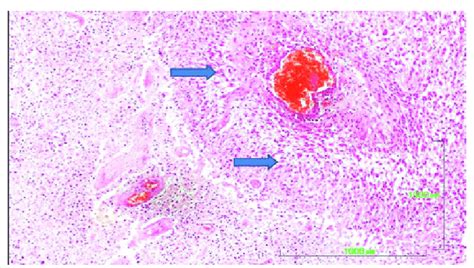

Alright, so when we talk about pseudopalisading necrosis , we’re essentially describing a very specific pattern of cell death observed under a microscope. Think of it as a visual cue for pathologists. Necrosis itself means cell death, which is a natural process in the body, but it can also happen due to injury or disease. Now, pseudopalisading is the really interesting part. Imagine a bunch of cells, like little soldiers, lining up in a row, or ‘palisade,’ around an area where other cells have died off – the necrotic core. This arrangement isn’t a true palisade formed by living cells trying to protect something; instead, it’s an artifact, a sort of illusion created by the way the cells react to the dying tissue. These lining cells are often tumor cells, and their arrangement around the necrotic zone is a tell-tale sign. This pattern is a hallmark of certain types of aggressive tumors, most notably glioblastoma , a very serious type of brain cancer. The cells closest to the necrotic area are starved of oxygen and nutrients, leading to their death. The cells that survive then get pushed outwards, creating that characteristic palisaded appearance. It’s like a frantic huddle of survivors around a disaster zone. This isn’t just a random scattering of dead cells; it’s an organized, albeit morbid, display that provides crucial diagnostic information. The presence of pseudopalisading necrosis strongly suggests a high-grade malignancy, prompting further investigation and guiding treatment strategies. It’s one of those microscopic features that can really change the game in terms of diagnosis and prognosis. So, remember, it’s the arrangement of cells around a necrotic area that gives this phenomenon its name and its diagnostic weight. It’s a complex dance of life and death at the cellular level, signaling underlying aggressive disease processes that need our attention.

So, you’re probably wondering, where exactly does this peculiar pattern of pseudopalisading necrosis pop up? While it can appear in various pathological scenarios, it’s most famously and frequently associated with malignant gliomas , particularly the most aggressive form, glioblastoma multiforme (GBM) . This is the big one, guys. GBM is notorious for its rapid growth and tendency to infiltrate surrounding brain tissue, and pseudopalisading necrosis is a key histological feature that helps pathologists identify it. But it’s not only GBM. You might also see this pattern in other high-grade gliomas, like anaplastic astrocytomas or anaplastic oligodendrogliomas, though it’s less common and usually less pronounced than in GBM. Beyond brain tumors, pseudopalisading necrosis can sometimes be observed in other types of cancers that have a tendency to outgrow their blood supply and develop necrotic centers. Think about some metastatic tumors that have spread to the brain from elsewhere in the body, like lung or breast cancer, although this is less typical. It can also, albeit rarely, be seen in non-neoplastic conditions, such as certain types of infarction (tissue death due to lack of blood flow) or even in some reactive processes. However, when a pathologist spots this classic arrangement, their mind immediately goes to glioblastoma or other high-grade gliomas. The reason it’s so linked to these aggressive tumors is their rapid proliferation. Tumor cells grow so fast that they often outstrip their blood supply, leading to areas of cell death (necrosis) in the center. The surviving tumor cells on the periphery then arrange themselves in that characteristic palisade around the dead zones, trying to expand outwards. This histological finding is crucial because it helps differentiate these aggressive tumors from lower-grade ones, which typically lack significant necrosis and vascular proliferation – another common feature in GBM. So, while the pattern can appear elsewhere, its strongest association and diagnostic significance lie squarely within the realm of aggressive brain tumors. It’s a really important clue in the diagnostic puzzle.